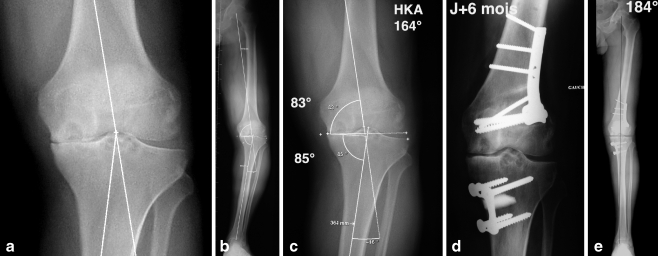

Fig. 3.

A 40-year-old male patient. a Medial osteoarthritis with necrosis of the medial condyle. b Severe varus deformity. c Centred X-rays with a hip–knee–ankle (HKA) angle of 164°, medial distal femoral mechanical angle (MDFMA) of 83° and the medial proximal tibial mechanical angle (MPTMA) of 85°. d Radiological result. Notice after six-months follow-up, no malunion of the distal femur and proximal tibia and the good healing of the osteotomies as well as the osteonecrosis of the medial condyle. e Postoperative goniometry of the patient after undergoing a double level osteotomy (DLO). Notice the HKA angle of 184°